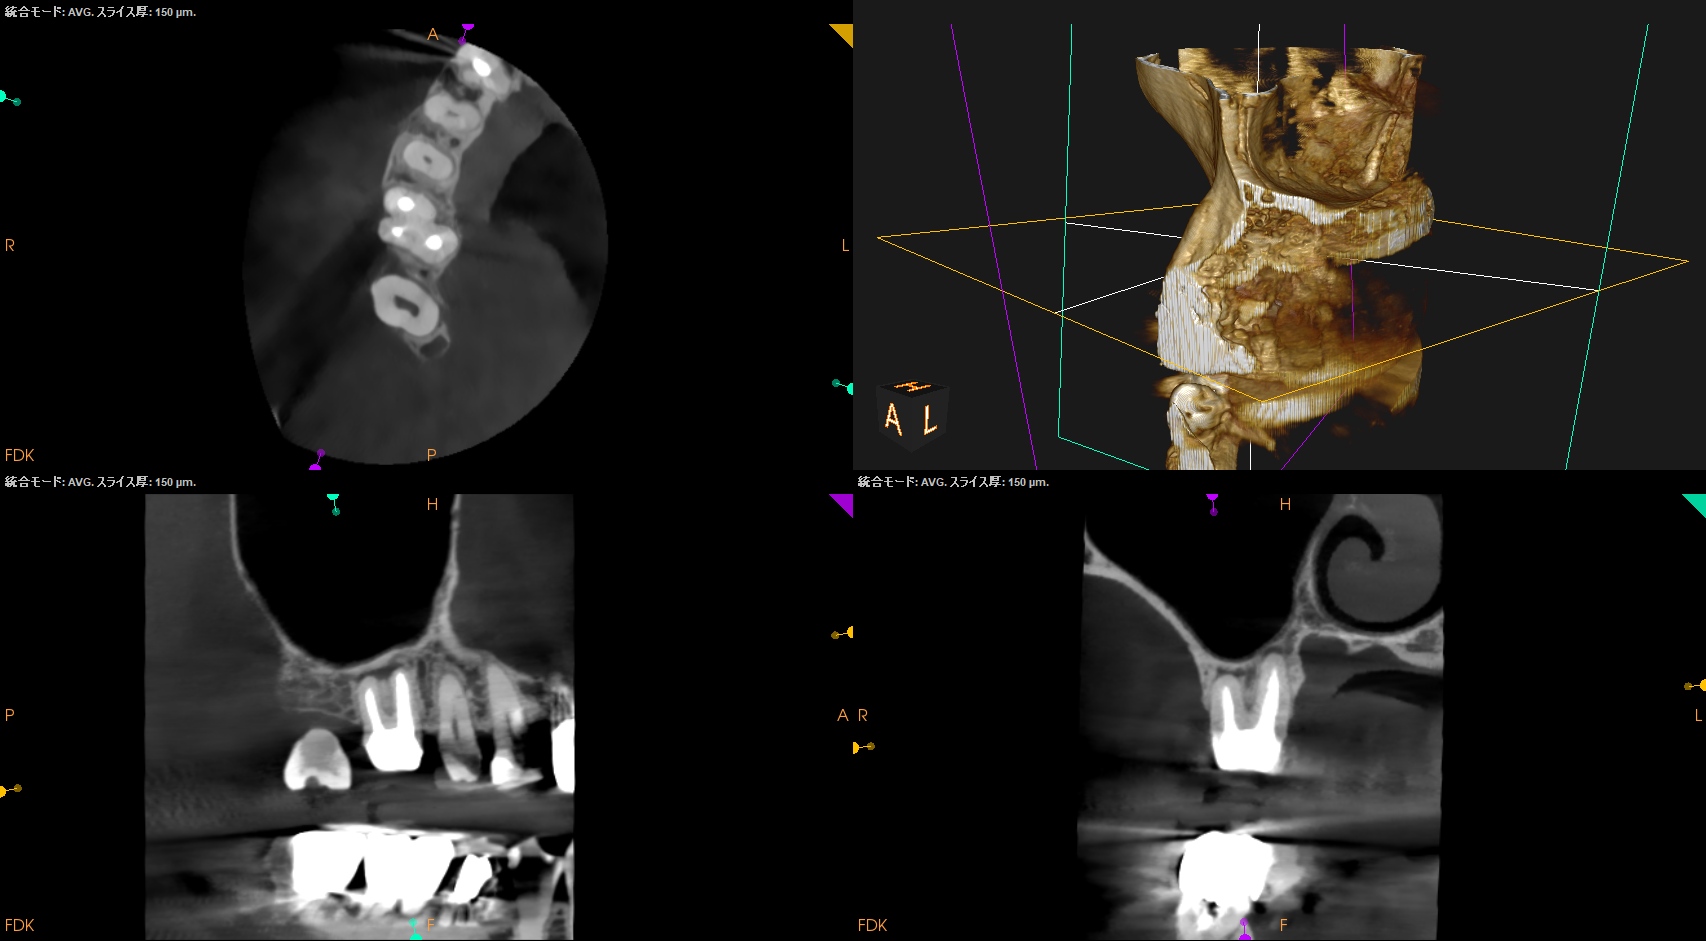

CBCT(2024.7.1)

#3

MB

DB

P

MB,DB,Pと3根全てに病変がある。

しかも形成が不完全だ。

再根管治療が濃厚である。

#14

MB,DBには病変がないが、Pに存在する。

これは頭が痛い。

パラタルフラップも困難なケースだからだ。

#16